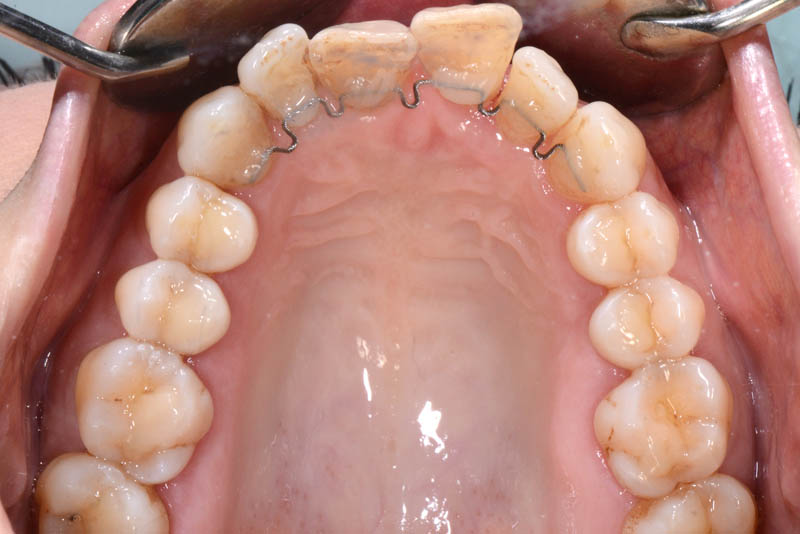

Following an initial phase of non-surgical periodontal therapy aimed at removing subgingival calculus, Dr. Anna Mariniello performed both upper and lower alignment using a lingual, non-bracket orthodontic technique, employing active retainers applied to the lingual surfaces of the teeth.